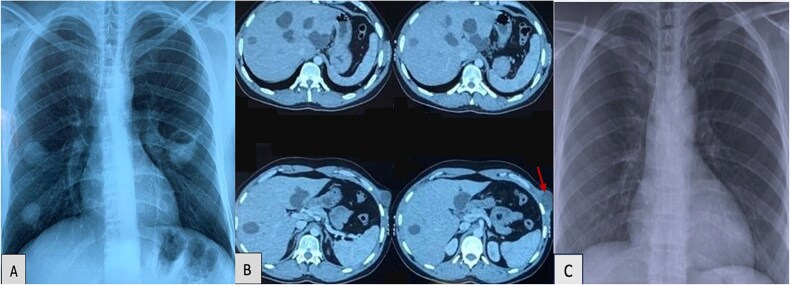

Clinical image: multiple pulmonary, hepatic and Abdominal Wall hydatid cysts.

临床表现:多发肺、肝、腹壁包虫病。